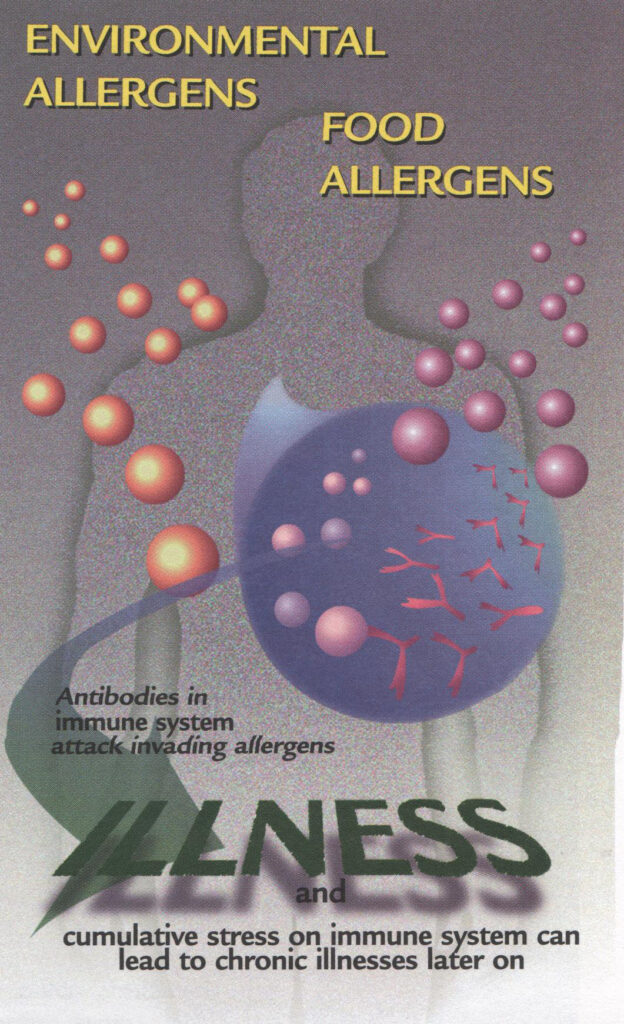

Other friendly bacteria may thrive unless broad-spectrum antibiotic drugs attack them.

Lactobacilli are known to produce natural antibiotics of their own.

For instance, the Probiotics L. acidophilus manufactures antibiotic-like enzyme agents’ called acidolin, acidophilin, and lactocidin; L. brevis makes lactobacillin and lactobrevin, and L. bulgarious produces bulgarican.

Of these, the antimicrobial enzymes acidophilin and bulgarican are most effective against food born pathogens.

Anytime an imbalance in the gut leads to the overgrowth of one bacterial species of another, Probiotics supplementation with a good, viable acidophilus should be considered.